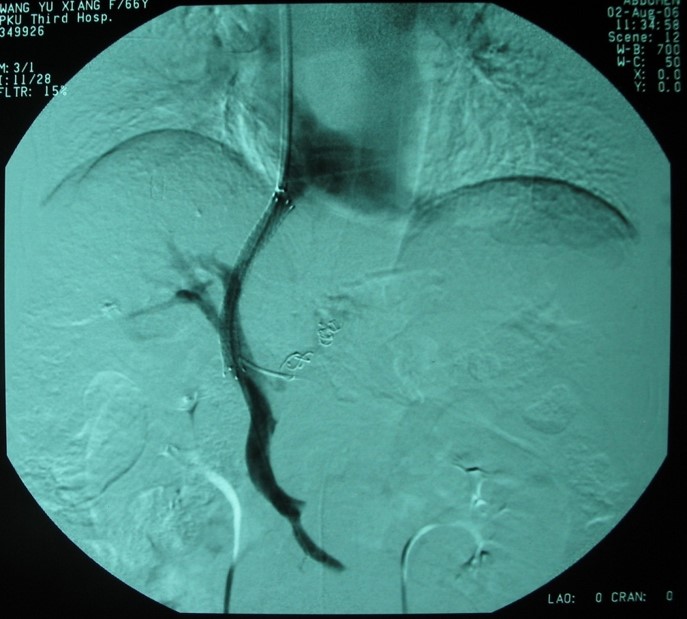

肝靜脈壓力梯度測(cè)定

門靜脈高壓治療

tips手術(shù)治療前

tips手術(shù)治療后